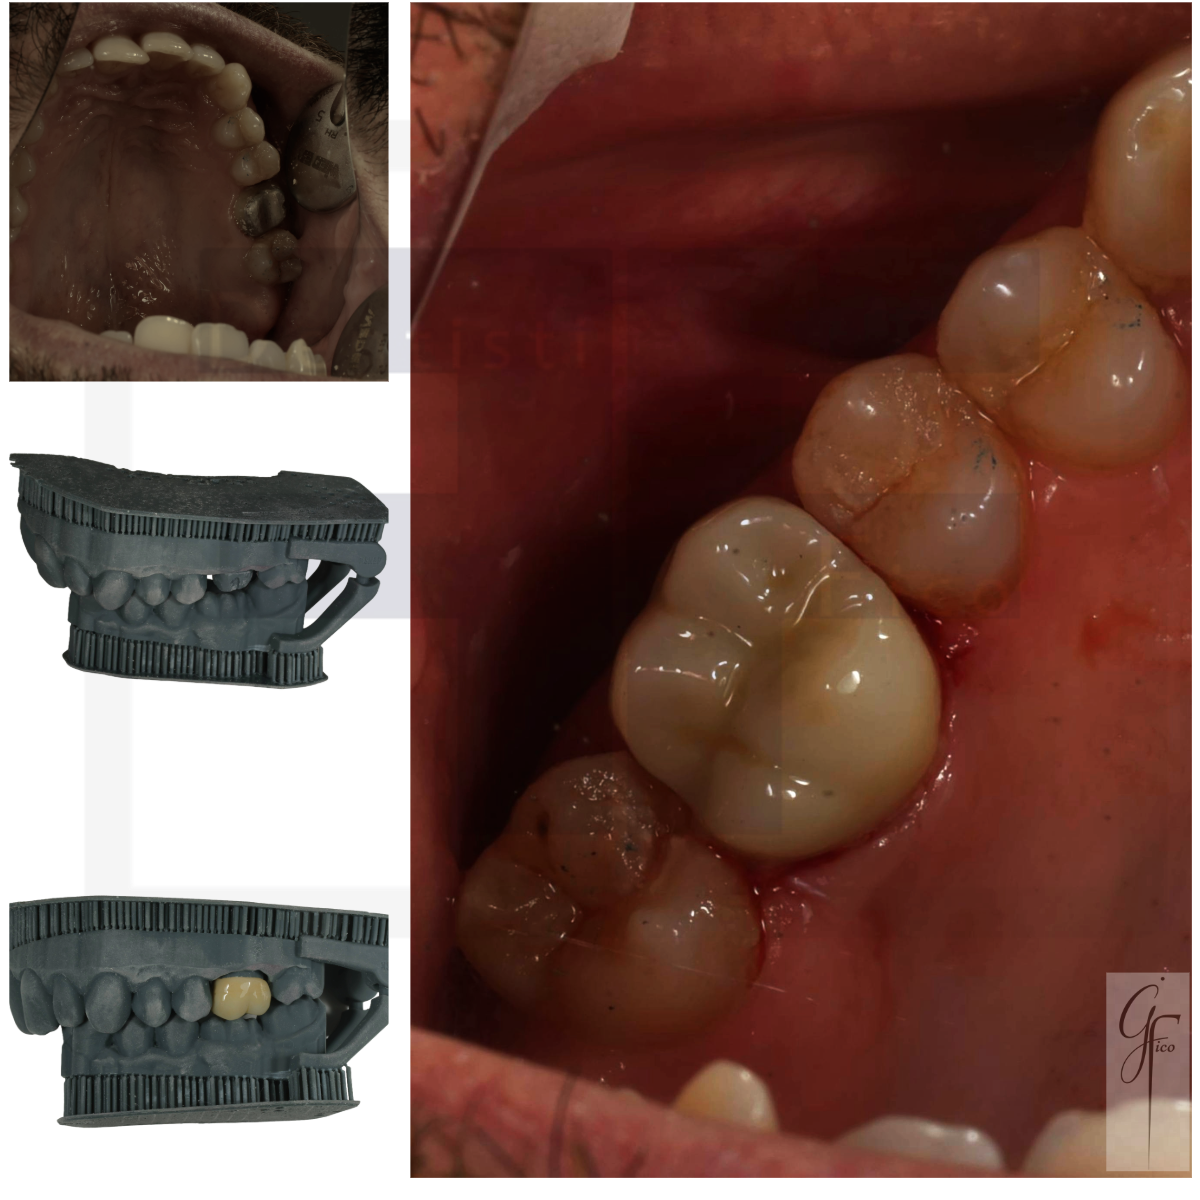

Negli ultimi anni l’odontoiatria ha vissuto una vera rivoluzione grazie all’introduzione degli scanner intraorali e dei flussi digitali. L’impronta tradizionale con materiali da impronta è stata progressivamente affiancata e, in molti casi sostituita, dall’impronta digitale.

Lo scanner intraorale permette di acquisire un modello tridimensionale estremamente preciso delle arcate dentali, eliminando disagi per il paziente e migliorando l’efficienza del processo clinico e di laboratorio.

È fondamentale però chiarire un punto: lo scanner è uno strumento, non un sostituto del ragionamento clinico.

La qualità dell’impronta digitale dipende da:

- Corretta preparazione del moncone

- Gestione dei tessuti molli

- Controllo dell’umidità

- Capacità di lettura critica dell’immagine digitale

- Conoscenza dei limiti dello strumento

Un clinico esperto sa riconoscere un dettaglio marginale non perfettamente acquisito, sa quando ripetere una scansione, sa interpretare correttamente ciò che vede sul monitor.